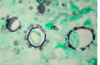

Q

Name the diagnosis

A

Mickey Mouse and ships wheel - paracocci

How does it appear on microscopy?

Yeast colonies appear, variable size, mother cell surrounded by multiple buds Mickey mous apparence, ships wheel